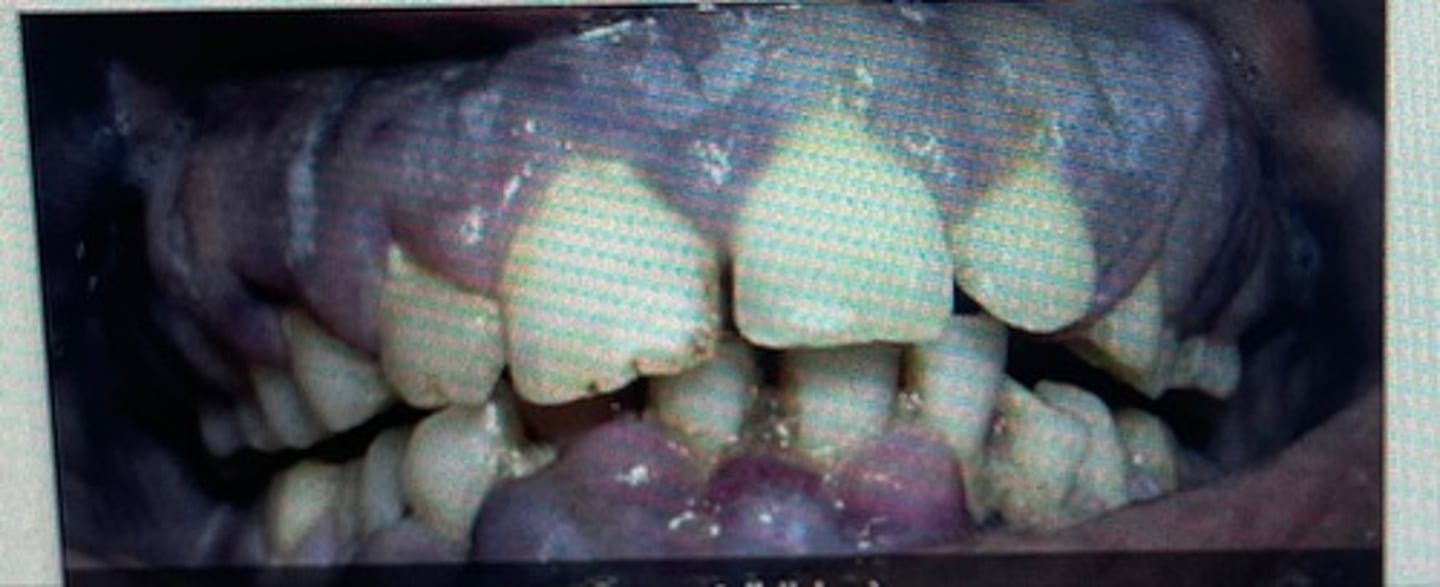

pink

pigmented

erythematous

cyanotic

pale pink